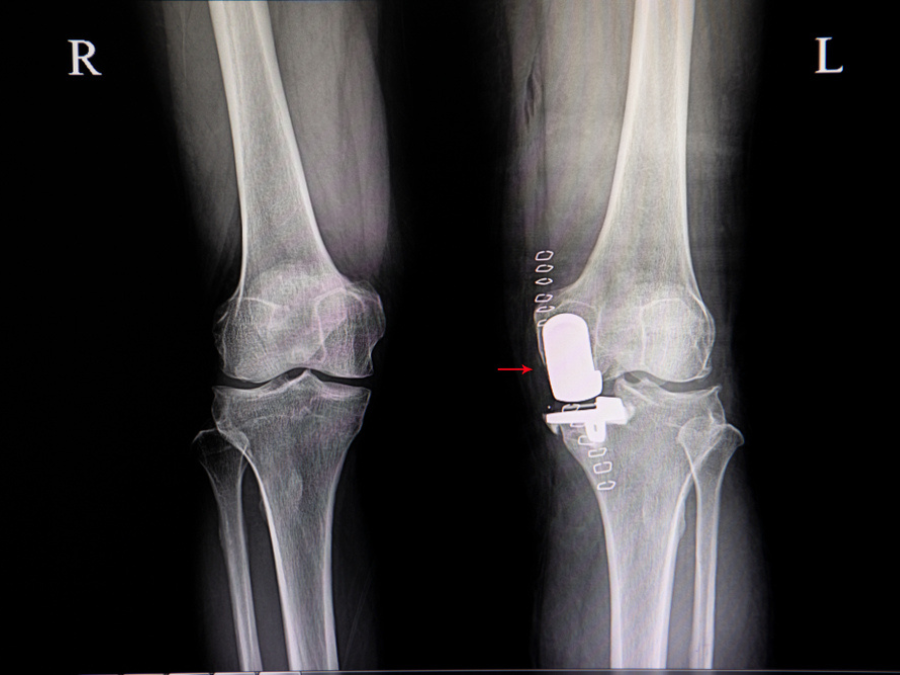

La protesi monocompartimentale, chiamata anche unicompartimentale o parziale, interviene su una porzione specifica del ginocchio. L’articolazione presenta tre comparti distinti: mediale, laterale e femoro-rotuleo. In molte persone l’artrosi interessa un solo compartimento , spesso il mediale.

Durante la visita valuto mobilità, asse dell’arto, qualità dei legamenti e distribuzione del carico. Le immagini radiografiche e la risonanza magnetica permettono di comprendere l’estensione dell’usura e guidano la scelta terapeutica.

Com’è fatta una protesi monocompartimentale

La protesi monocompartimentale è composta da componenti realizzati con materiali che  garantiscono resistenza, scorrevolezza e integrazione con l’osso.

Il sistema comprende:

• una componente femorale in lega metallica (cromo-cobalto o titanio)

• una base metallica posizionata sulla parte superiore della tibia

• un inserto in polietilene.

La componente femorale sostituisce la parte usurata del condilo, mentre la componente tibiale offre una superficie stabile  su cui si ancora un inserto in polietilene ad alta resistenza. Al di sopra di esso scorre la componente femorale della protesi.